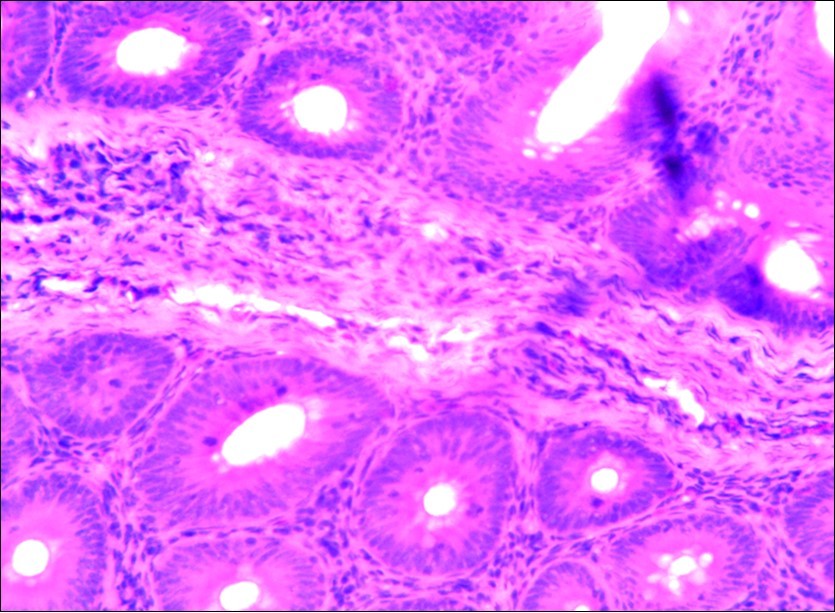

In this study, the reduction in oocyst count observed in the treated group was compared with amprolium could be attributed to the presence of a bioactive compounds azadiractin A which is known to bind membrane cholesterol, altering the integrity of the parasite membrane, resulting in loss of homeostasis and eventual death of the parasite 29]. Also, limonoids contained in NeemAzal® inhibit protein digestion and uptake of vitamins and minerals by the parasites in the gut 17. This action results in impaired nutrient utilization, reduced growth, and multiplication of the parasite which could contribute to the reduced oocyst count observed. Extracts of neem and mahogany when used individually have been reported to reduce oocyst count in avian coccidiosis 11,12. The observed reduction in oocyst count and the significant increase in weight gain of the birds when treated with NeemAzal®, as compared with the negative control group could probably be due to the inhibition of inflammation in the intestinal mucosa which is suggestive of an increased nutrient absorption across the intestinal wall and enhanced feed conversion ratio compared to the negative control this is in agreement with reports by Nwosu et al.12 and Biu et al.11 who also reported an increased weight gain and feed conversion ratio in birds treated with only Khaya senegalensis extracts and Azardiractaindica, respectively. The observed increase in RBC and haemoglobin concentration is indicative of the erythropoieticability of the NeemAzal®, which is beneficial since the Eimeria parasite in the epithelia of the intestines causes bloody diarrhoea and consequently anaemia (Table 1). This finding is in consonance with 15 who reported an anti-anaemic effect of Khaya Senegalensis on phenyl hydrazine-induced anaemia in rats. Neem has been shown to possess anti-anaemic properties in rats 14. The significant increase in mean weight gain in treated birds when compared to the negative control is possibly due to the inhibition of inflammation in the intestinal mucosa which is suggestive of an increased nutrient absorption across the intestinal wall and enhanced feed conversion ratio compared to the negative control. Nwosu et al.12 and Biu et al.11 reported an increased weight gain and feed conversion ratio in birds treated with only Khaya Senegalensis andAzadiractaindica extracts, respectively. In a similar study, Neem acts like toltrazuril exhibiting anticoccidial. In addition, exposure of broiler chickens to 20000 Oocysts of Eimeria tenellacaused generalized degeneration of the caecal glands with massive Oocysts and gametocyts within the caecal glands with fibrosis (Figure 3, Figure 4 & Figure 5), however, broiler chickens treated with NeemAzal® post exposure to 20000 Oocysts of Eimeria tenella, shows equal numbers of caecal tissues with non-observable histopathological lesions (Figure 4), possibly due to the antioxidant and anti-coccidian effects of NeemAzal®. The exact mechanism of action of neem against coccidian parasites is unknown, but a report by the National Research Council 1992 30, suggested that aqueous neem leaf extract, when taken orally, produces an increase in red cells, white blood cells and lymphocyte counts thus enhancing the cellular immune response, increasing antibody production and so most pathogens can be removed before they cause the symptoms associated with disease this was in agreement with this study as seen in Table a remarkable increase of the RBCs.

Figure 3.Photomicrograph of caecum of chick uninfected and untreated showing no observable lesion X250 (H&E).

In addition, the generalized degeneration of the caecal glands, moderate numbers of gametocytes within the glandular regions with fibrosis which underscores reparative process in response to injury evoked by coccidiosis in the chicks which was perhaps brought about by the antioxidant and chemotherapeutic effect of NeemAzal®. The observed increase in RBC and hemoglobin concentration (Table 1) is indicative of the erythropoieticability of NeemAzal®, which is beneficial since the Eimeria parasite in the epithelia of the intestines causes bloody diarrhea and consequently anaemia. This finding is in consonance with 15 who reported an anti-anaemic effect of Khaya senegalensis on phenyl hydrazine-induced anaemia in rats. If the results of this study are juxtaposed with the results of the previous studies on potent antioxidant, hepatoprotective and mitigative role of methanolic extracts of Azadirachtaindica,in both natural and experimental infection with Eimeria species and can be deduced that, NeemAzal® could be said to be a potent antioxidant, chemotherapeutic and tissue protective agent. This study also answered a question on further study advocated to determine the maximum safe levels of neem supplementation because the higher doses, due to its bitterness, may show adverse effects on feed intake which will change the performance parameters of birds (Figure 6 and Figure 7) . Light microscopic inspection of hematoxylin and eosin-stained sections revealed that the epithelial cells of the Cecum were infected by E. tenella(Figure 3 and Figure 4). The results of the safety study showed that exposure of chickens to NeemAzal® at 200mg/kg body weight did not alter the histoarchitecture of liver and kidney (Figure 6 & Figure 7) which is similar to the work conducted in the same environment by a group of Scientists 34. It is therefore recommended that NeemAzal® could be used as a coccidiostat to replace the expensive anti-coccidiostats in the market.